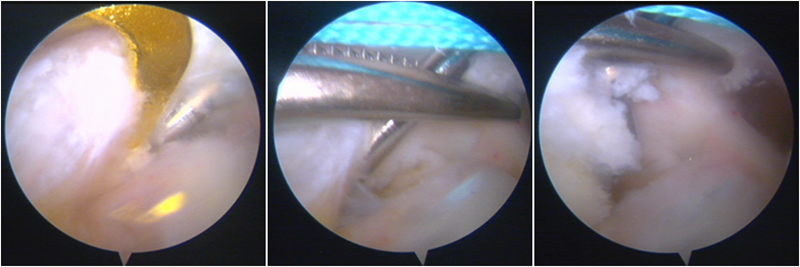

股骨侧保残骨道建立

股骨侧骨道建立,椭圆形扩孔保残9mm

韧带导入过程

送止血带后韧带表明血管膜